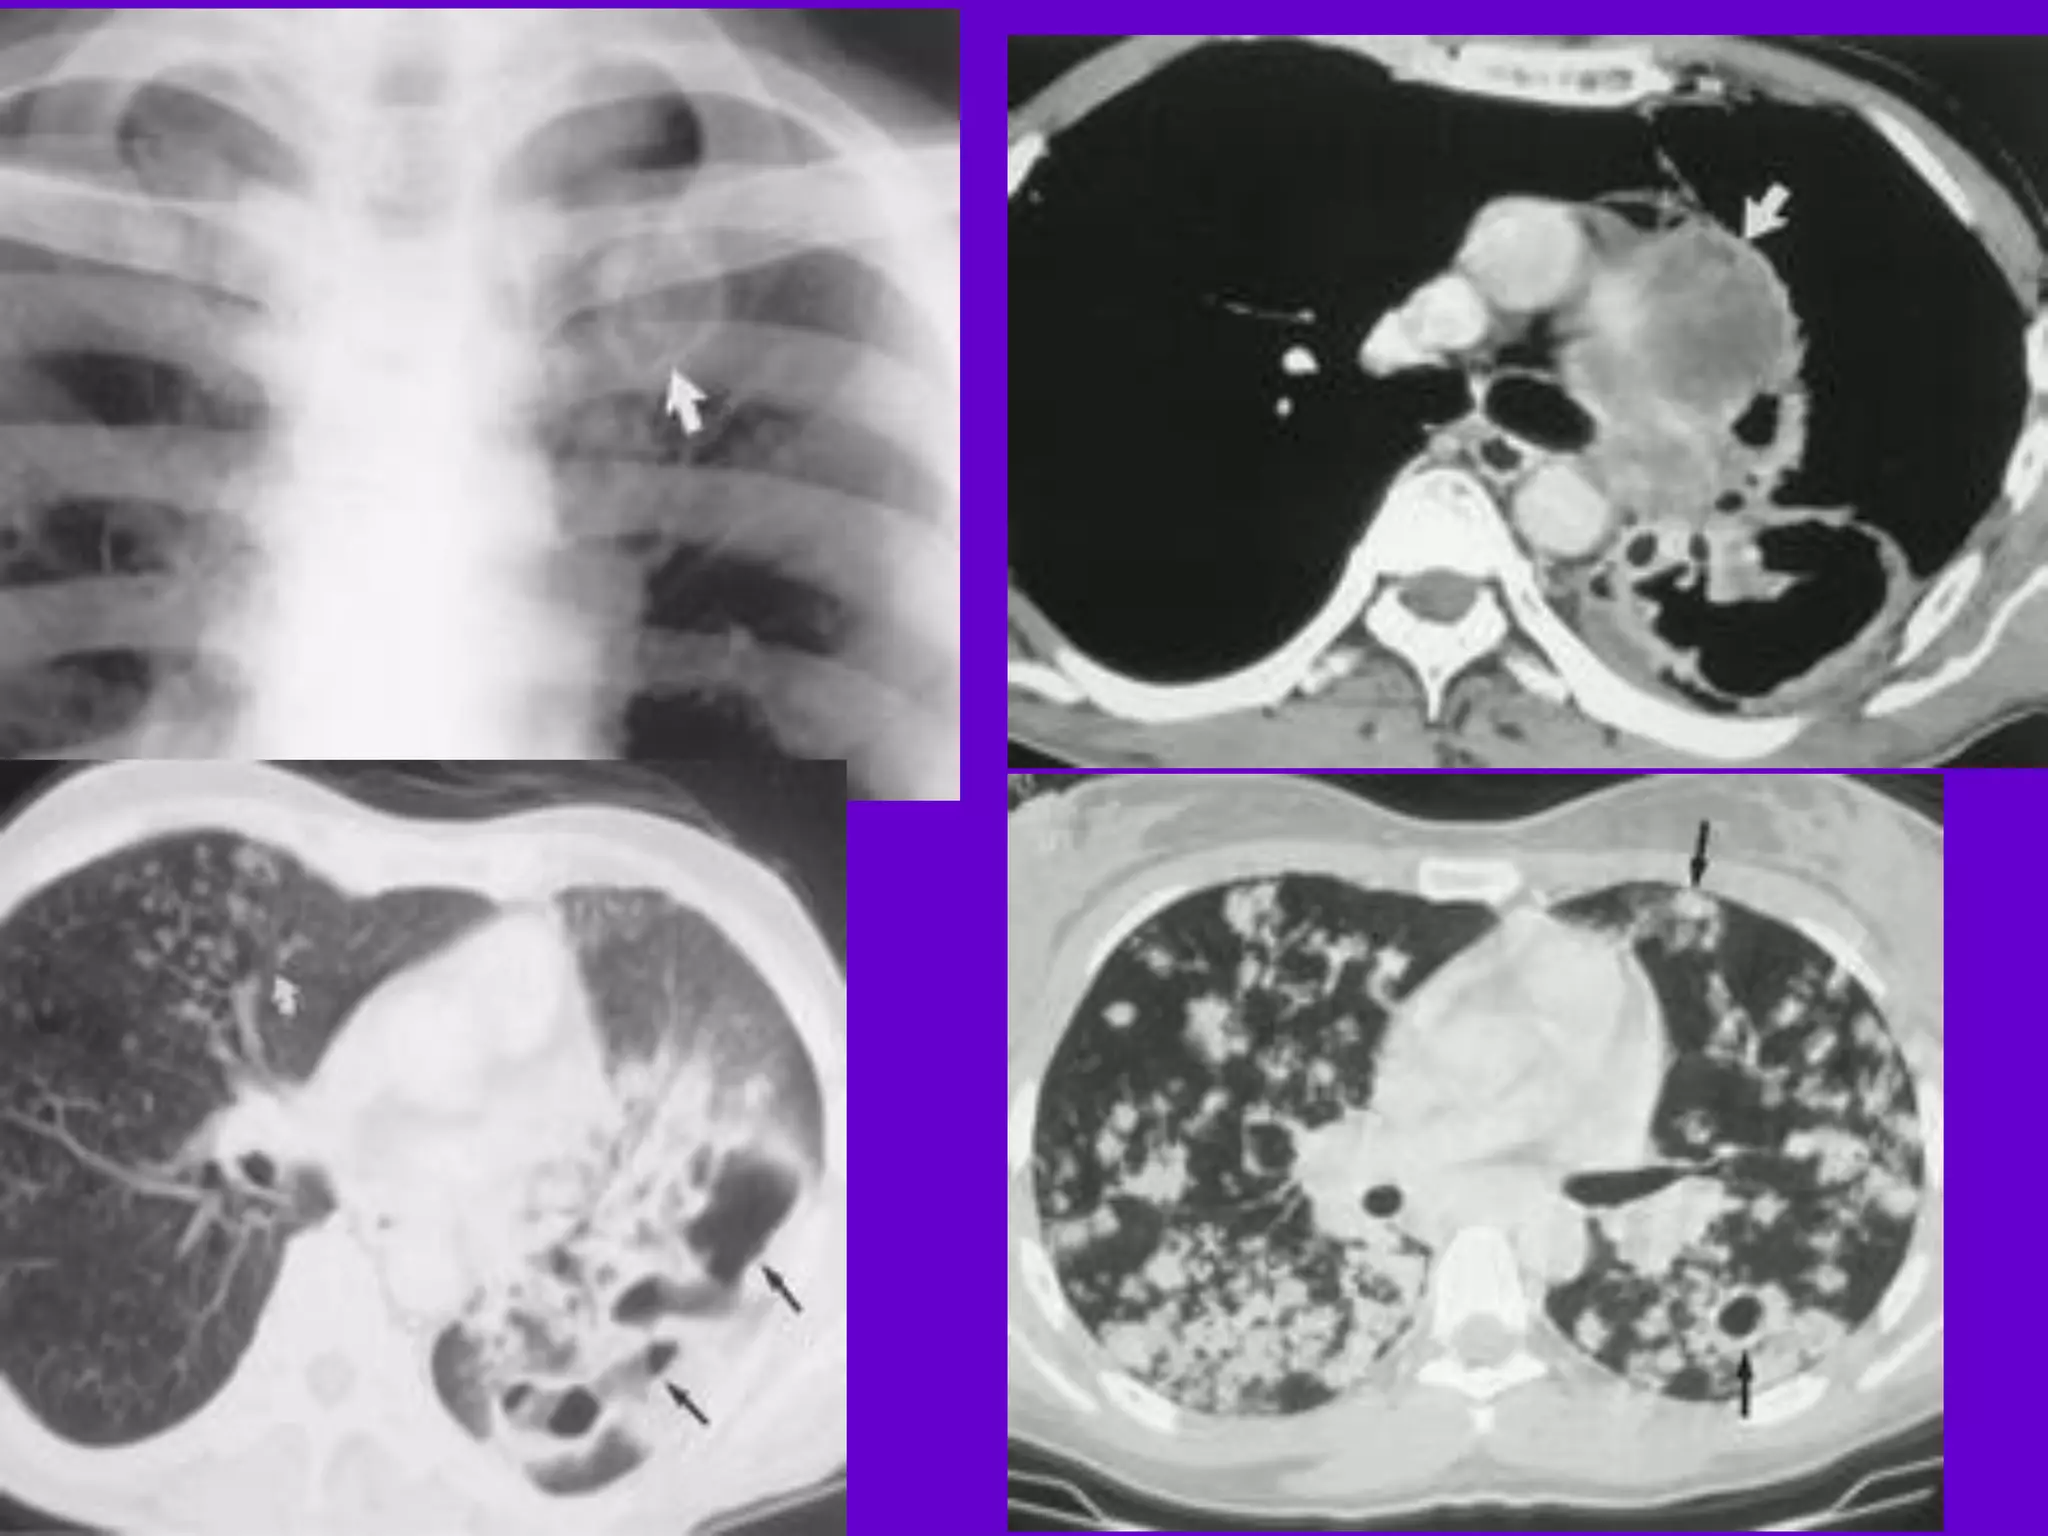

Bronchopneumonia

􀂄

On CT it is usually B/L and widespread,

not always

symmetrical involvement of lungs.

Hilar and Mediastinal

Lymphadenopathy

CT and MRI depict the hilar and

mediastinal LN

equally well.

􀂄 Calcification in the nodes is however

better seen on

CT.

􀂄 Necrosis is seen as focal areas of low

attenuation on

a CECT.

􀂄 On MRI focal necrosis is seen as areas

of increased

signal intensity on T2W images.

EBTB

HRCT is sensitive in the detection of

early

endobronchial spread of disease.

Miliary TB

􀂄 Earliest form of miliary TB is detectable

on HRCT.

􀂄 Coalescing nodules result into patchy

irregular

opacities and HRCT shows this variation

effectively

and has been described as “snowstorm

appearance”.

􀂄 HRCT shows cavitation, which is not

evident on plain

CXR.

Pleural Effusion 􀂄

􀂄 CT is sensitive to diagnose and define

even minimal

pleural effusion/pleural calcification.